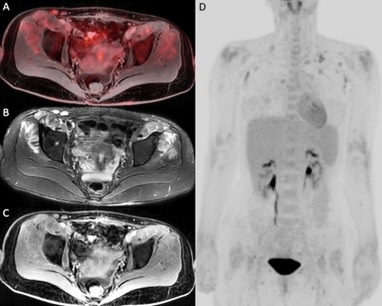

A 20-year-old male with biopsy-proven classical Hodgkin lymphoma, stage IVB. Baseline PET/ CT (a-c) and baseline PET/MR (d-e). At interim restaging PET/CT (f–h) and PET/MR (i-k), there was a concordant complete metabolic response, Deauville 2. The end of treatment study is not shown as there remained complete metabolic response. Incidental right-sided rib fractures persisted between staging and interim studies. SUV scale set between 0-8. Image courtesy of Cancer Imaging through CC BY 4.0.At staging, PET/CT detected 352 positive disease sites out of a potential 1,500 sites across 50 patients. PET/MRI detected 339 out of 352 true-positive sites, 1,148 true-negative sites, and 13 false-negatives sites. There was excellent intermodality agreement between PET/MRI and PET/CT, the researchers reported (k = 0.976, p < 0.001). There was also good correlation of disease site identification at interim assessment (k = 0.819, p < 0.001) and excellent correlation at end-of-treatment assessment (k = 1, p < 0.001), they reported.